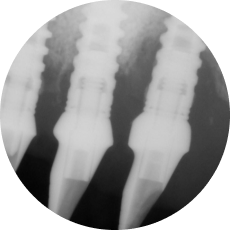

На примере постановки импланта на верхней челюсти в боковом фрагменте мы разберем частые ошибки, ведущие к развитию перииимплантита.

Критические ошибки имплантации в синусе

Герметичность соединения имплант-абатмент. Так ли это важно?